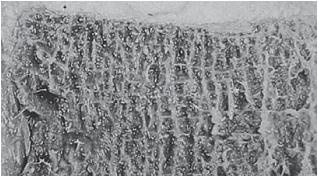

Не случайно я сравнил тело позвонка с драгоценным камнем. Это действительно драгоценный по функциям элемент позвонка. Дело в том, что тело позвонка состоит из губчатого вещества пористой структуры, которое образовано отдельными костными перекладинами — трабекулами (лат. trabecula — небольшая балка, перекладина), основой микроскопичного строения которых являются костные пластинки. Ячейки губчатого вещества тела позвонка заполнены красным костным мозгом. А красный костный мозг, как известно, это важнейший орган кроветворения и костеобразования, поскольку в его тканях находятся кроветворные элементы (стволовые клетки), клетки, разрушающие кость (остеокласты) и клетки, образующие кость (остеобласты). Ценность заключается в том, что именно от тела позвонка поступает регулярное и единственное питание для межпозвонкового диска через замыкательную (гиалиновую) пластинку, отделяющую губчатую кость тела позвонка от межпозвонкового диска.

Фото № 2. Наблюдается пористая структура тела позвонка в разрезе